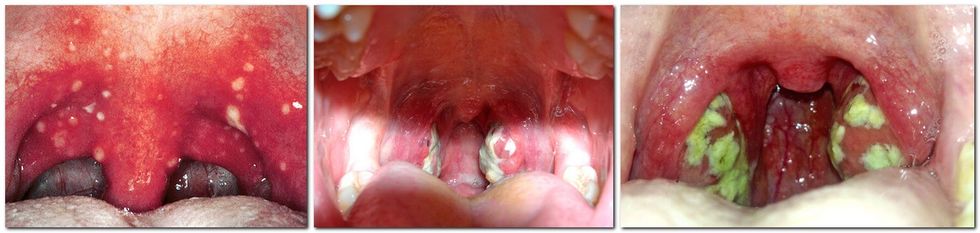

Angjinën me qelb kryesisht e shkakton streptokoku beta hemolitik i grupit A, ndërkaq sëmundja bartet nëpërmjet piklave.

Angjina fillon vrullshëm, me dhembje në gushë dhe me temperaturë të ngritur trupore nga 38 deri në 39 gradë Celsius.

Pacienti ka rrëqethje trupi, dhembje koke, humbje apetiti dhe molisje. Me vështirësi përpin ushqimin, për dallim nga angjinat virusale kur shfaqen thatësira e qiellzës dhe gërvishtja, transmeton Telegrafi.

Se a është fjala për angjinën me qelb, mjeku me përvojë mund të vlerësojnë në bazë të kontrollit të fytit, mirëpo më i rëndësishëm është veprimi diagnostik i marrjes së mostrës, sepse vetëm në bazë të analizës së saj mund të izolohet shkaktari.